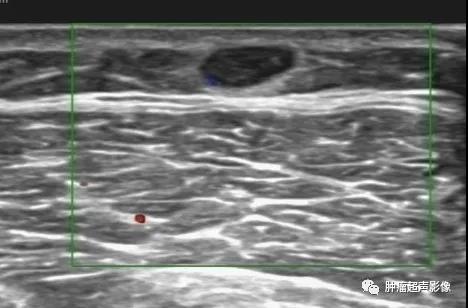

超声表现:一般呈低回声(少部分为高回声,胃血管球瘤一般都呈高回声,类似肝脏血管瘤表现),多为类圆形或椭圆形,边界清,较大肿瘤可显示其对指骨的侵蚀,内部及周边血流丰富,典型的呈花环状或小火球样,频谱呈低速低阻。

病理证实的血管球瘤,左大腿疼痛,超声显示皮下低回声,边界清,类圆形,少许血流,超声诊断比较困难,结合病史容易考虑血管平滑肌瘤。